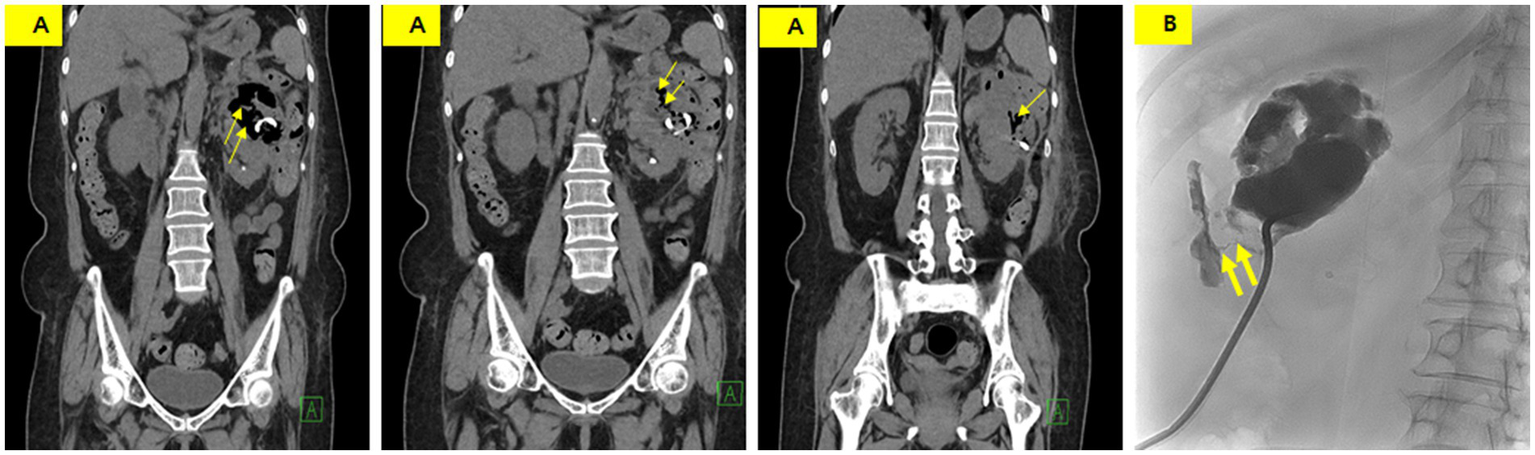

Figure 2

Follow-up CT showing an approximately 11 cm perinephric abscess with peripheral enhancement, medial displacement of the left kidney, and adjacent edematous changes in the descending colon.

Non-enhanced CT was performed on the 24th day of hospitalization because of poor drainage and a color change in the drainage. CT showed a decreased size of the perinephric abscess but new air bubbles within it and an edematous change in the descending colon (Figure 3A). These findings strongly suggested the formation of a fistula between the abscess and the descending colon. A tubogram via the PCD catheter revealed a fistula between the perinephric abscess and the descending colon (Figure 3B).

Figure 3

(A) Non-enhanced CT showing a slightly decreased abscess size with new intralesional air (thin arrow) and an indistinct boundary between the perinephric abscess and descending colon. (B) Tubogram demonstrating an abscess pocket measuring 7 cm in length, with a fistula tract (thick arrow) showing contrast entering the descending colon.